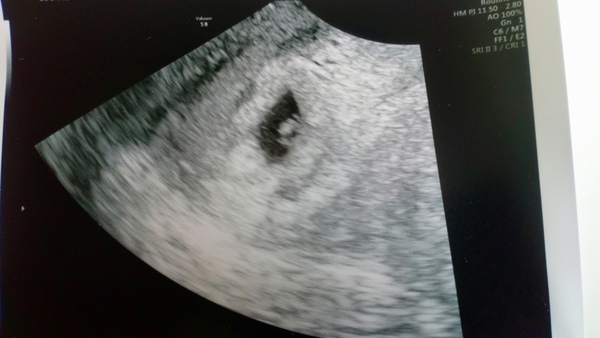

My scan was good! Little tiny blob with little tiny heartbeat, measuring 4.8mm so right for 6+1. Happy and surprised, but not taking this as being home safe- last pregnancy we saw the heartbeat at 7 weeks then lost the baby at 13 (incidentally, same sonographer today as at 13 weeks last time). Cramping doesn't necessarily mean bad news!